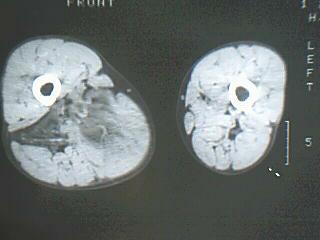

患者 男 34岁 右腿肿物。98年右侧外伤致股骨骨折,手术治疗,2001年二次手术(取钢板),发现大腿内侧有鸡蛋大小样肿块,无明显疼痛不适,2007年开始发现肿物明显增大,无发烧,无红肿。

病灶巨大,内见脂肪影,考虑软组织肿瘤,脂肪肉瘤?恶性纤维组织细胞瘤?

右侧大腿内侧肌间含脂性巨块,密度不均,内见软组织成分及条管状钙化,错构瘤伴出血?真性或假性脂肪瘤

病灶巨大,内见脂肪影,考虑脂肪肉瘤

脂肪肉瘤可能大